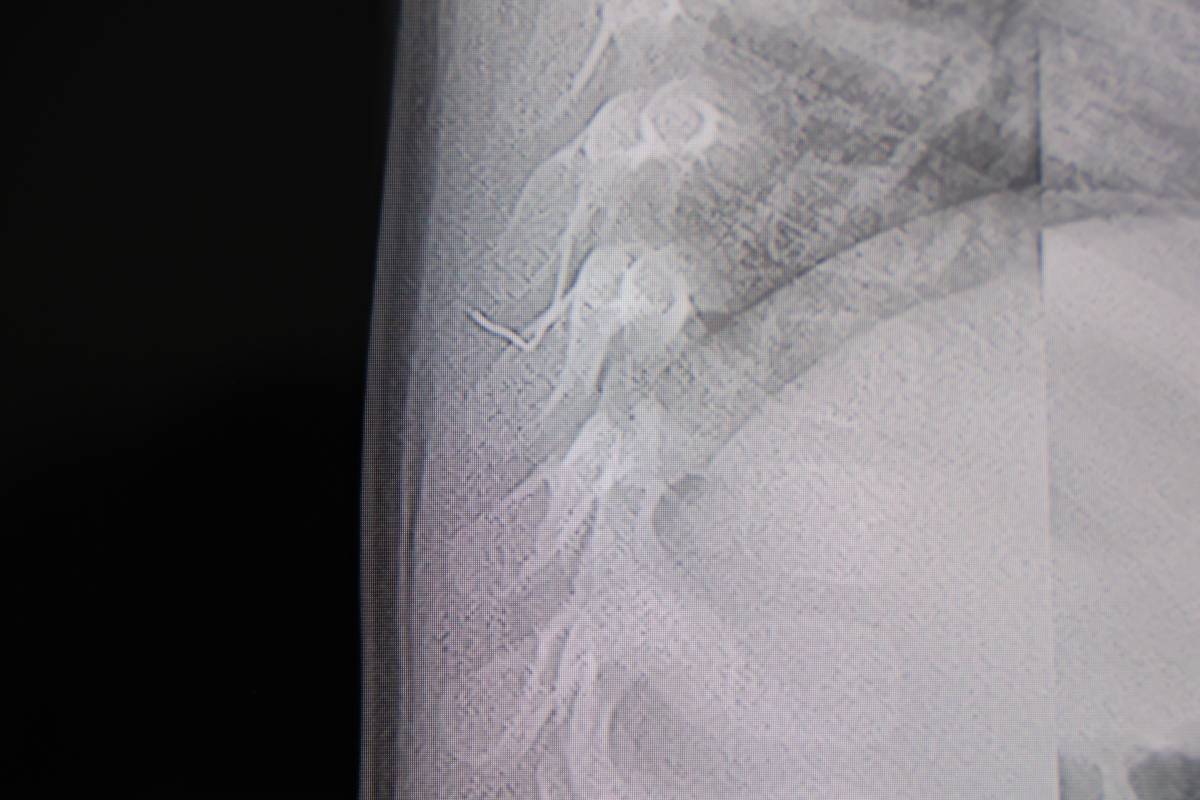

Ameliyat sırasında çıkarılan yabancı cismin, ince zımba teline benzer metal bir tel olduğu belirlendi. Yaklaşık 2 santimetre uzunluğundaki bu telin, sırt bölgesinde zamanla ilerleyerek ciddi sağlık sorunlarına yol açabileceği kaydedildi. Cismin çıkarılmasının ardından bebeğin rahatladığı ve huzursuzluk belirtilerinin azaldığı gözlemlendi.

Operasyonu gerçekleştiren Prof. Dr. İdris Altun, konuya ilişkin yaptığı açıklamada, “Sırtında yabancı bir cisim olduğu söylenmiş ancak çıkarılamayacağı ve 8 yaşına kadar beklenmesi gerektiği ifade edilmişti. Bize başvurduğunda yaptığımız tetkiklerde, cilt altında, omurilik kanalına çok yakın ve akciğer zarına doğru ilerleyen bir yabancı cisim tespit ettik” ifadelerini kullandı.

Yabancı cismin yana doğru ilerlemesi halinde akciğer zarına ve akciğere batma riskinin bulunduğunu vurgulayan Prof. Dr. Altun, bu durumun enfeksiyonlara ve ilerleyen süreçte tümörle karışabilecek tablolara neden olabileceğini söyledi. Yapılan erken müdahalenin, bu risklerin önüne geçtiği kaydedildi.